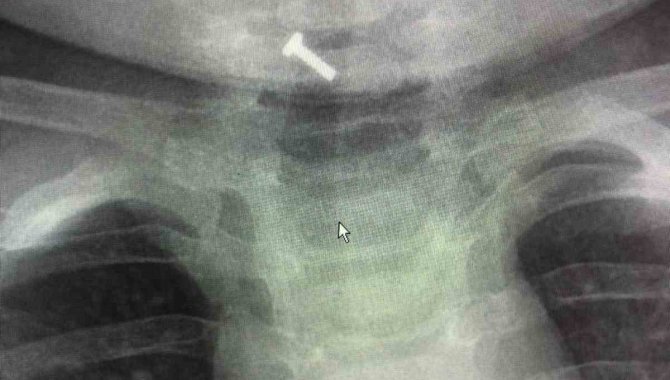

Elazığ'da yutkunma şikayetiyle ailesi tarafından hastaneye başvurulan 9 aylık bir bebeğin boğazına kaçan oyuncak parçası başarılı bir operasyonla çıkartıldı.

Elazığ'da 9 aylık bir bebek yutkunma da sorun yaşaması üzerine Fırat Üniversitesi Hastanesine başvurdu. Bunun üzerine 9 aylık bebek Fırat Üniversitesi Hastanesi Çocuk Gastroenteroloji Hepatoloji ve Beslenme Bölümüne sevk edildi. Burada da tetkik ve ön kontroller sonrası bebeğin boğazında oyuncak parçası olduğu tespit edildi. Gastroenteroloji Hepatoloji ve Beslenme Bilim Dalı Başkanı Prof. Dr. Yaşar Doğan ve ekibi tarafından yapılan endoskopik operasyon ile 9 aylık bebeğin boğazına kaçan oyuncak parçası başarılı operasyonla çıkartıldı. 9 aylık bebeğin sağlık durumun iyi olduğu bildirildi.